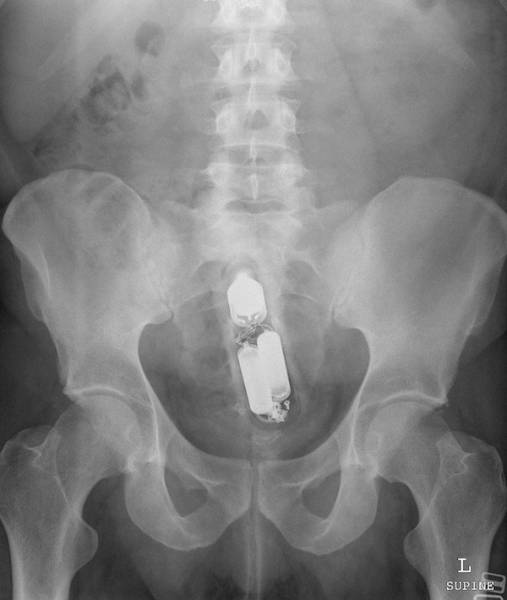

Man puts wire up his rectum to get stuck wine bottle.

Both get stuck. As ever.